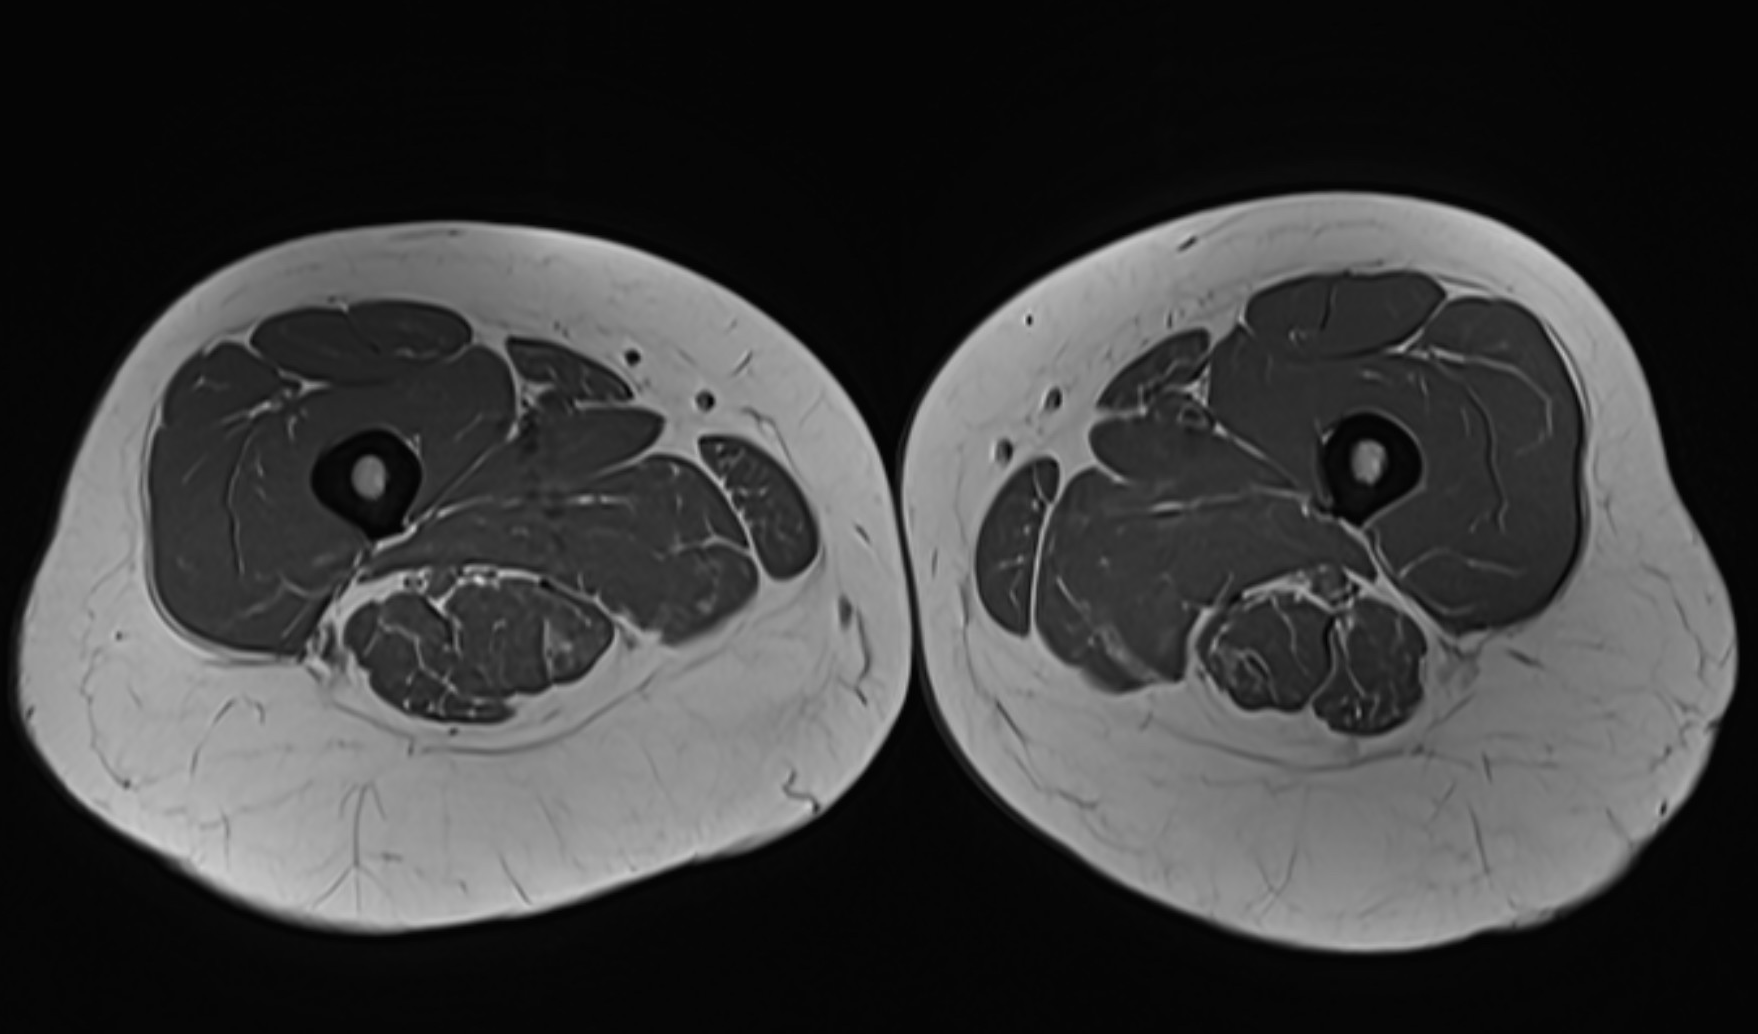

The femur (thigh bone) is the longest and strongest bone in the body – a central structure for walking, load and movement. Despite its strength, the femur can suffer from fractures, stress reactions, infections, tumors or inflammations that affect both function and quality of life. With a magnetic resonance imaging (MRI) examination of the femur, you get a very detailed picture of the skeleton, bone marrow, muscles, tendons and surrounding soft tissues. The examination is completely radiation-free, painless and particularly useful when other imaging methods have not provided sufficient information.

An MRI examination of the femur is an accurate way to diagnose hidden injuries or diseases in the skeleton and soft tissues. The examination is completely painless, takes approximately 20–30 minutes and does not require a referral. The images are reviewed by a specialist and a written report is delivered within a few days.